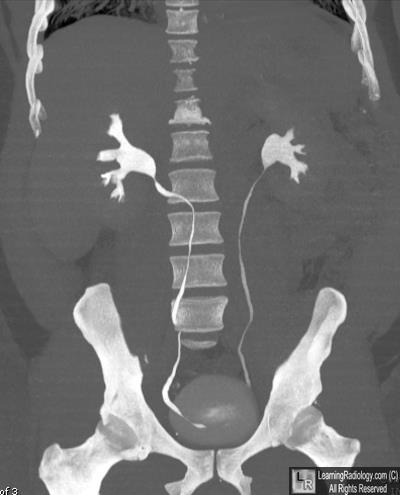

Coronal Reformatted CT Urogram

- Retrocaval ureter

3. Retrocaval ureter

RetroCaval Ureter

- Also known as “circumcaval ureter”

- Abnormality in embryogenesis of IVC

- Results from abnormal persistence of right subcardinal vein positioned ventral to ureter in the definitive IVC

- Developing right ureter courses behind and medial to the IVC